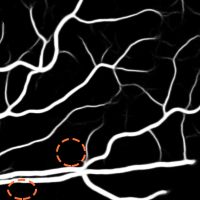

4.1 Validation of the Base System

We started by evaluating our Base System regarding data augmentation, prediction and regularization. The results of each variant are shown in Table 3, while the probabilistic predictions can be seen in Fig. 4. All tests were performed under the same conditions, with the only source of variability being the component under study.

4.1.1 Data Augmentation

To validate the procedure described in Section 2.4, we studied four alternatives. At first, we reduced the total number of patches per image to 3000, by not performing data augmentation – No Augmentation. Then, we increased the total number of patches to 12000 in three different ways. In the first case, we oversampled the image by extracting 9000 more original patches – Oversampling. In the second one, the remaining 9000 patches were artificially created by non-linearly deforming each patch, as described in (Oliveira et al.,, 2017) – Elastic Samples. Each set of 3000 elastic patches was obtained using a different combination: , , or . These values were found manually, ensuring that both the artificial samples and their respective annotations retain a consistent appearance. Finally, we used 9000 rotated patches, as in the Base System, but we placed them consecutively (not randomly) – Consecutive Rotations.

Considering the Base System as the reference, we can see that reducing the number of patches by four strongly deteriorated the results in terms of Acc and AUC. Besides this, either when using original or elastic patches to keep the initial number of samples, the differences to the reference remained almost the same. Looking directly at Fig. 4, we notice that these approaches favored the simultaneous appearance of FN and FP, with elastic patches leading to greater tortuosity in the detected vessel segments. Overall, this hints that the network benefited the most from the information encoded by the rotations. Another important note is related to the way those rotations were presented to the network. Recalling section 2.4, we have seen that some data augmentation strategies designed for FC-CNNs (Dieleman et al.,, 2016; Worrall et al.,, 2016) require the rotated versions to be arranged consecutively. The Consecutive Rotations test hints that a deterministic proximity between the rotated patches is detrimental to the performance of the FCN, with the network showing more difficulties in detecting vessel segments as can be seen in Fig. 4.

When facing the randomly placed rotations used in the Base System, all the alternatives were found to be prejudicial with statistical significance.